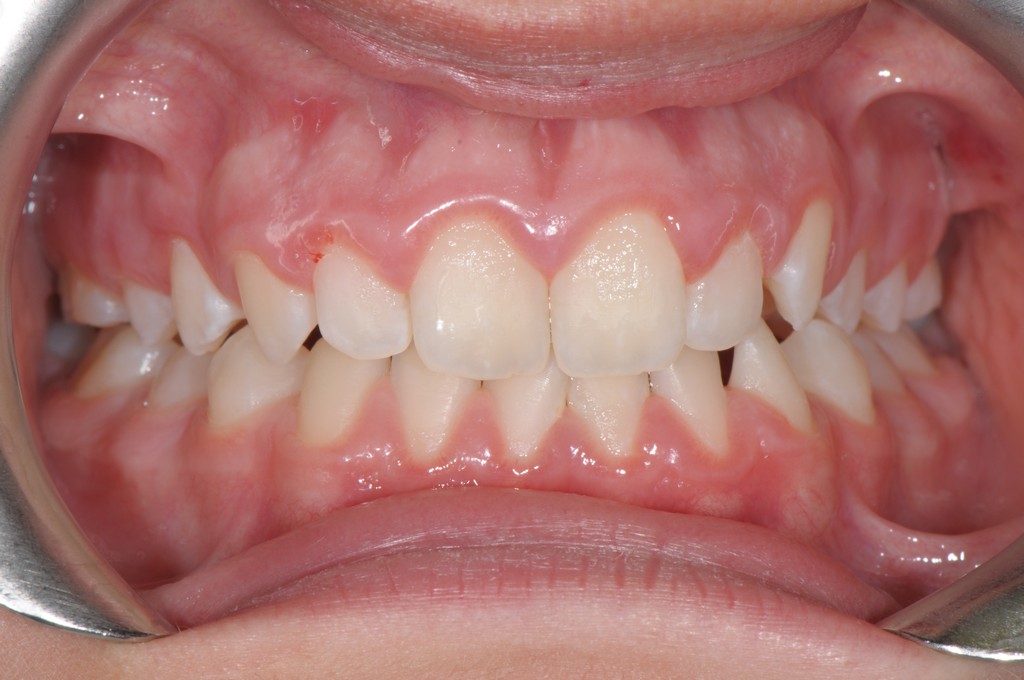

L'apparato stomatognatico, complesso "sistema multifunzione" costituito dalle basi mascellare e mandibolare, dalle arcate dento-alveolari, dal sistema neuro-muscolare e dalle articolazioni temporo-mandibolari, concorre all'espletamento di funzioni vitali per l'individuo, quali deglutizione, respirazione, fonazione e masticazione.

A differenza della Terapia Ortodontica Fissa che si preoccupa soprattutto dell'allineamento dentario, la Terapia Miofunzionale Ortognatodontica Biodinamica si preoccupa di ricreare la funzione, dalla quale ne conseguirà il corretto sviluppo dell'organo. Essa riveste piena dignità scientifica, grazie alle più moderne acquisizioni in tema di crescita e di fisiologia neuromuscolare.

Quest'approccio terapeutico, che "integra contemporaneamente la terapia ortognatodontica e la terapia miofunzionale", mira a correggere le alterazioni funzionali nel bambino e nell'adolescente trattando nel contempo la malocclusione, così come sostenuto dall'Associazione Italiana Miofunzionale Ortognatodontica Biodinamica, tramite l'utilizzo di apparecchiature ortognatodontiche funzionali quali la PFGB, la PFGB2 e la contemporanea messa in atto di esercizi di terapia miofunzionale.